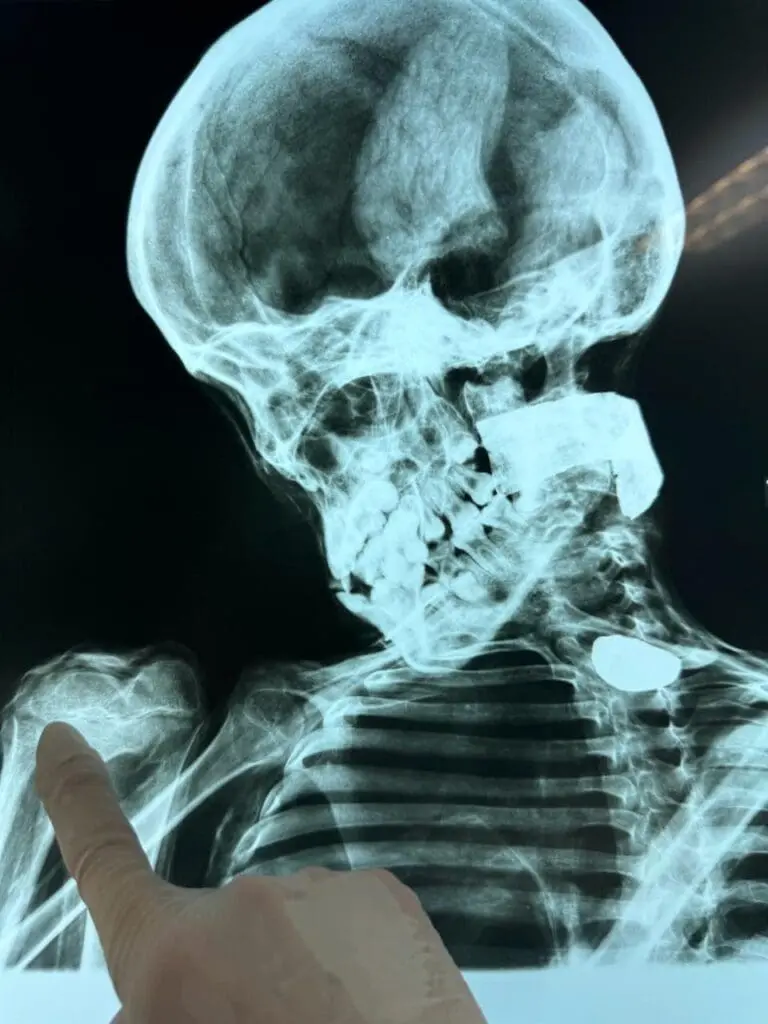

Forensic Examination of the Nazca Specimens

On Easter morning of 2024, my father, Dr. John McDowell and I were headed to Peru to examine the tridactyl mummies. We were going with two other renowned forensic specialists, and Max, my wiz-kid teenage camera man. Dr. John McDowell is a forensic odontologist, recently retired professor from the University of Colorado School of Dentistry and School of Medicine. Here is a recent bio prepared for his reception of the Gradwohl medallion, https://www.aafs.org/article/dr-john-mcdowell-named-2024-rbh-gradwohl-laureate

We were fortunate enough to have two of the best forensics experts in the world make the trip with us. Dr. James Caruso, M.D. a forensic pathologist and Chief Medical Examiner of the City and County of Denver, and Dr. William Rodriguez, a forensic anthropologist at the Maryland State Medical Examiner. The doctors came as volunteers, on their own time, to begin the forensic examination of the mummies.